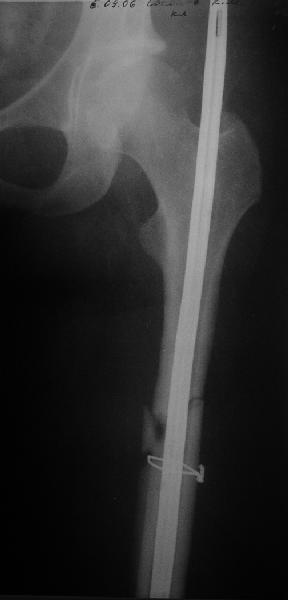

фото несращения бедра